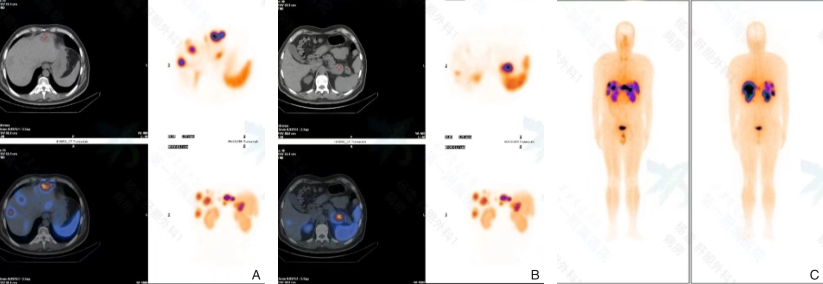

图3 患者299mTc-TOC全身显影结果Fig.3